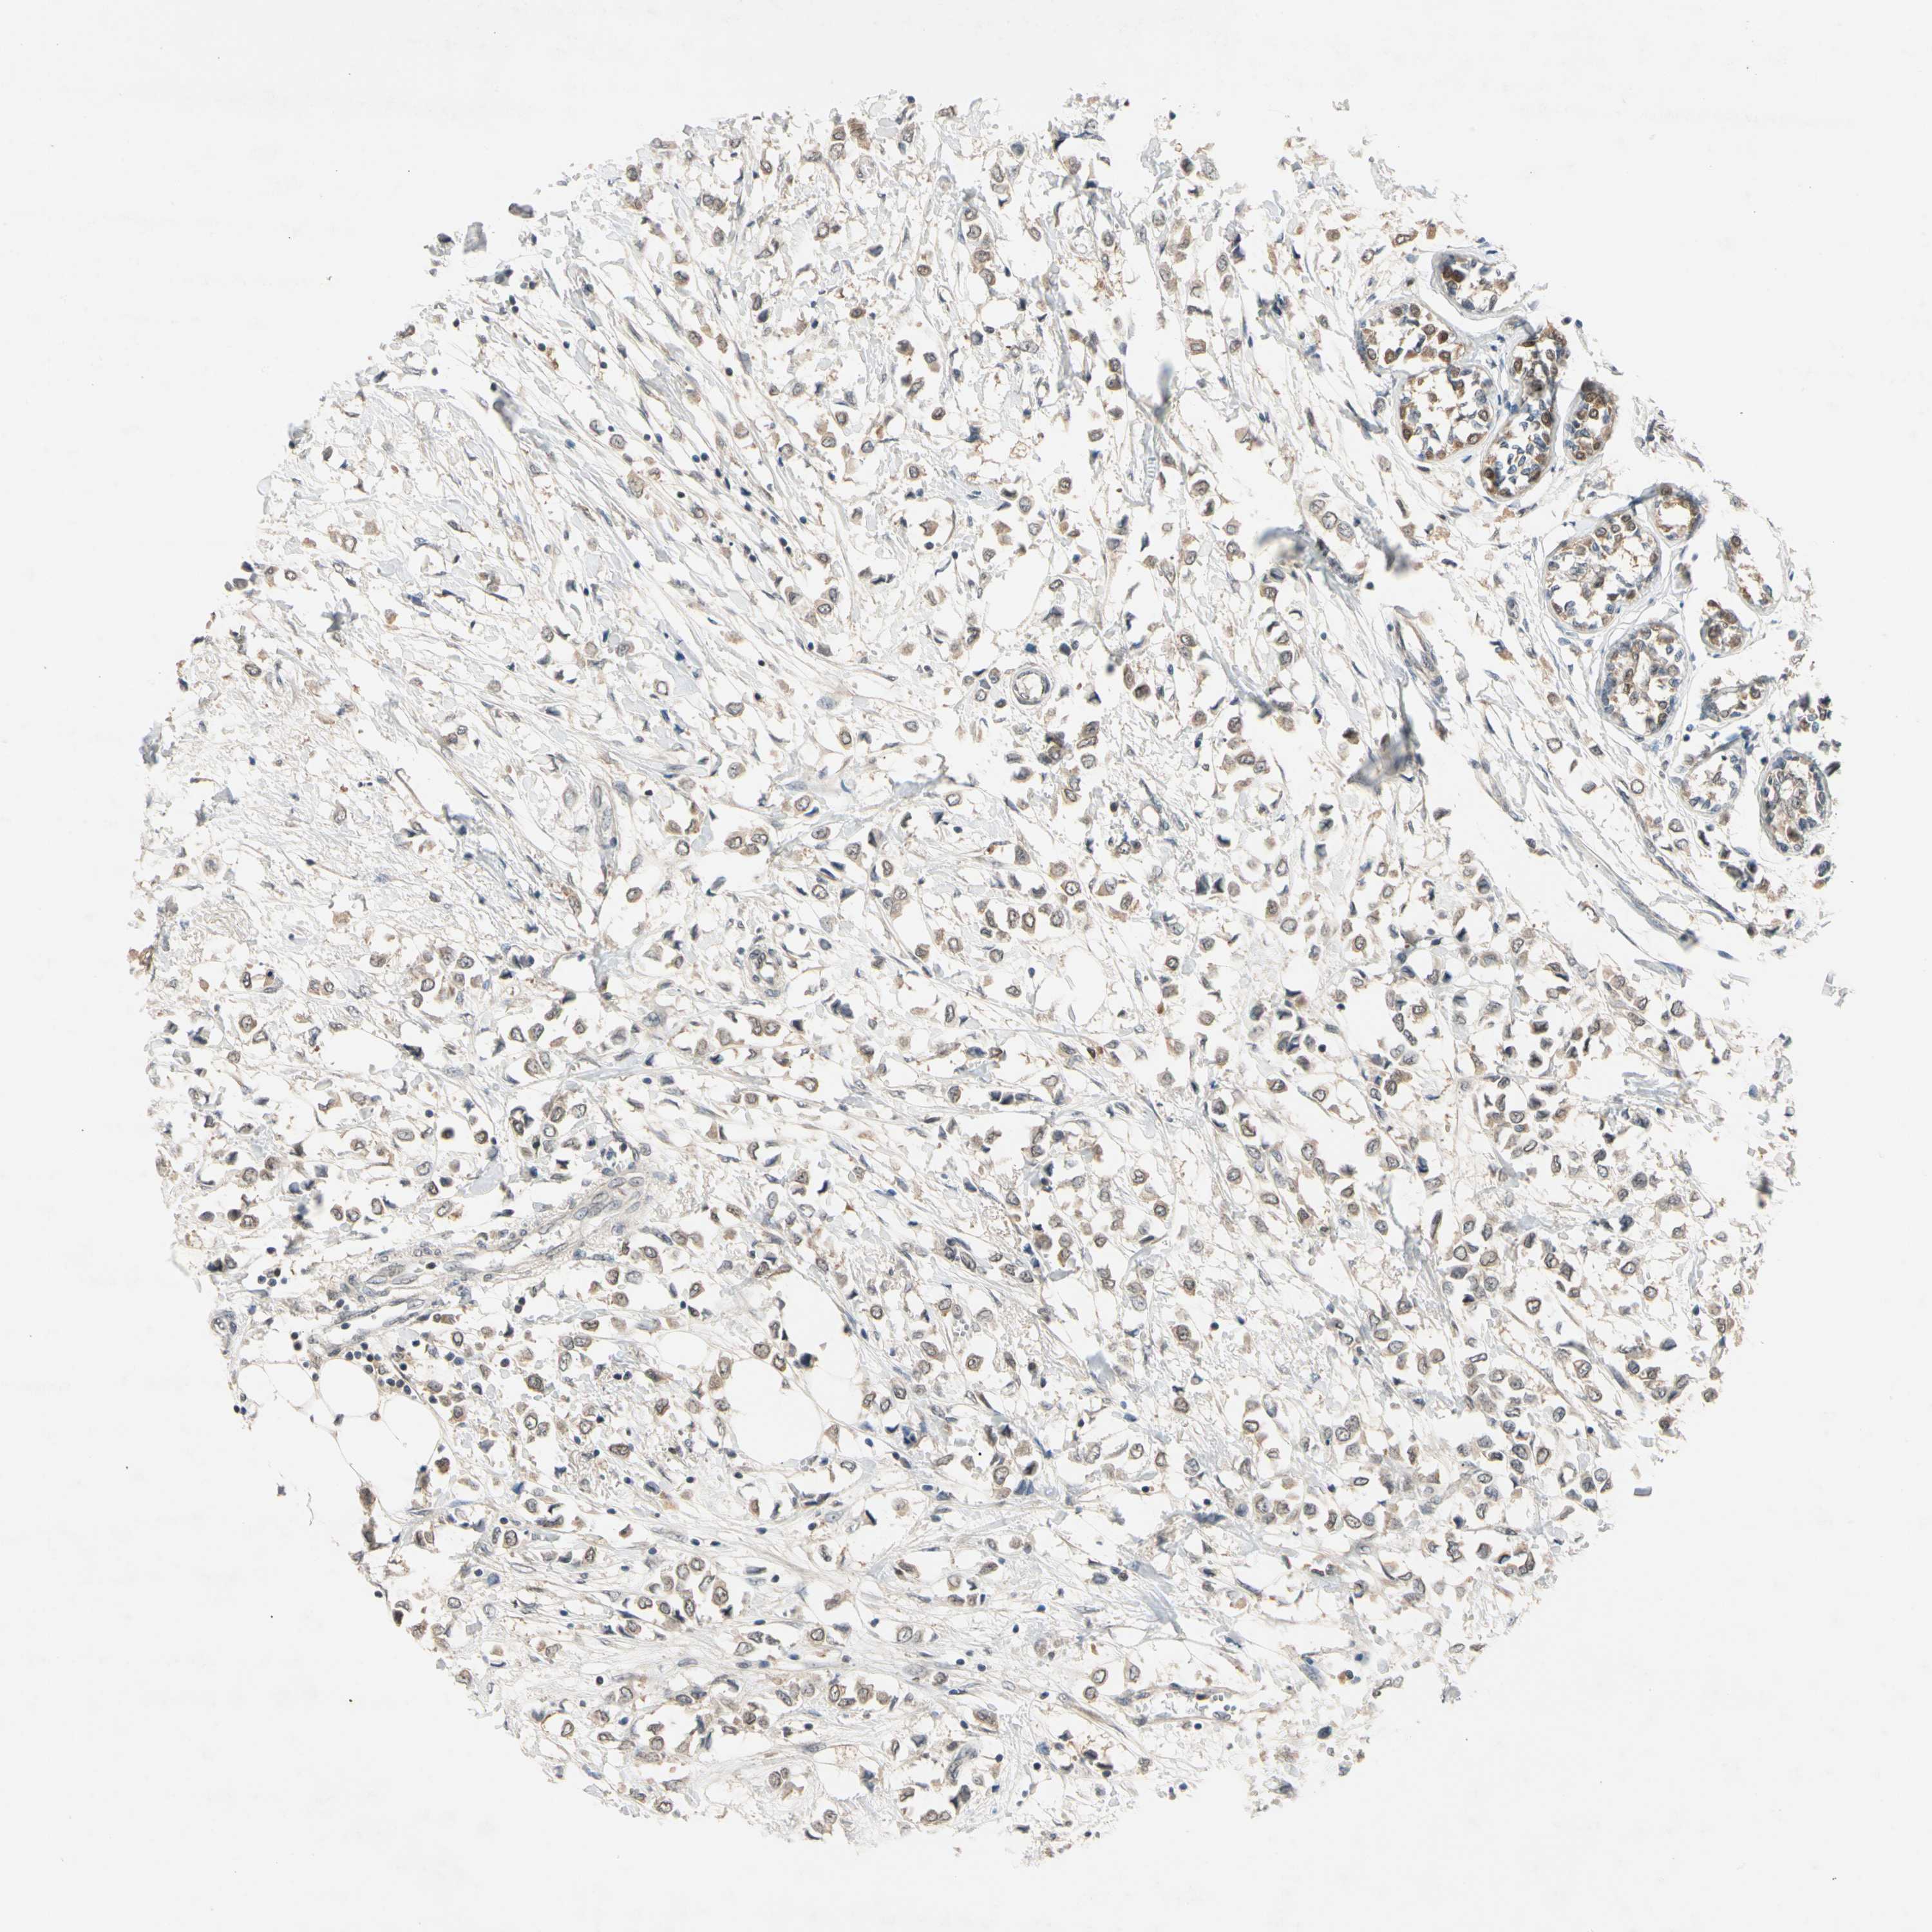

BRCA TCGA BRCA VALIDATION PROTEIN EXPRESSION